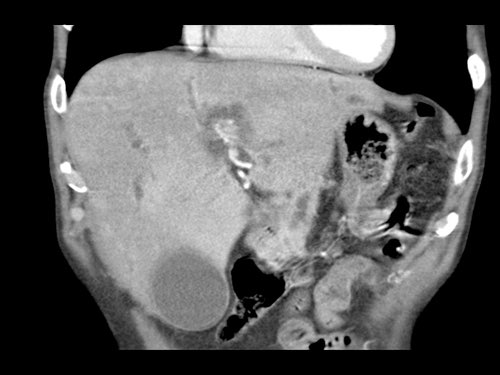

Tái tạo mặt phẳng coronal cho thấy:

- Bất thường bờ viền thành SMV được nhận thấy rõ hơn trên tái tạo coronal này (mũi tên).

- Khối u ở thân tụy (đầu mũi tên trắng).

- Huyết khối trong các nhánh bên của SMV (mũi tên xanh nhỏ).